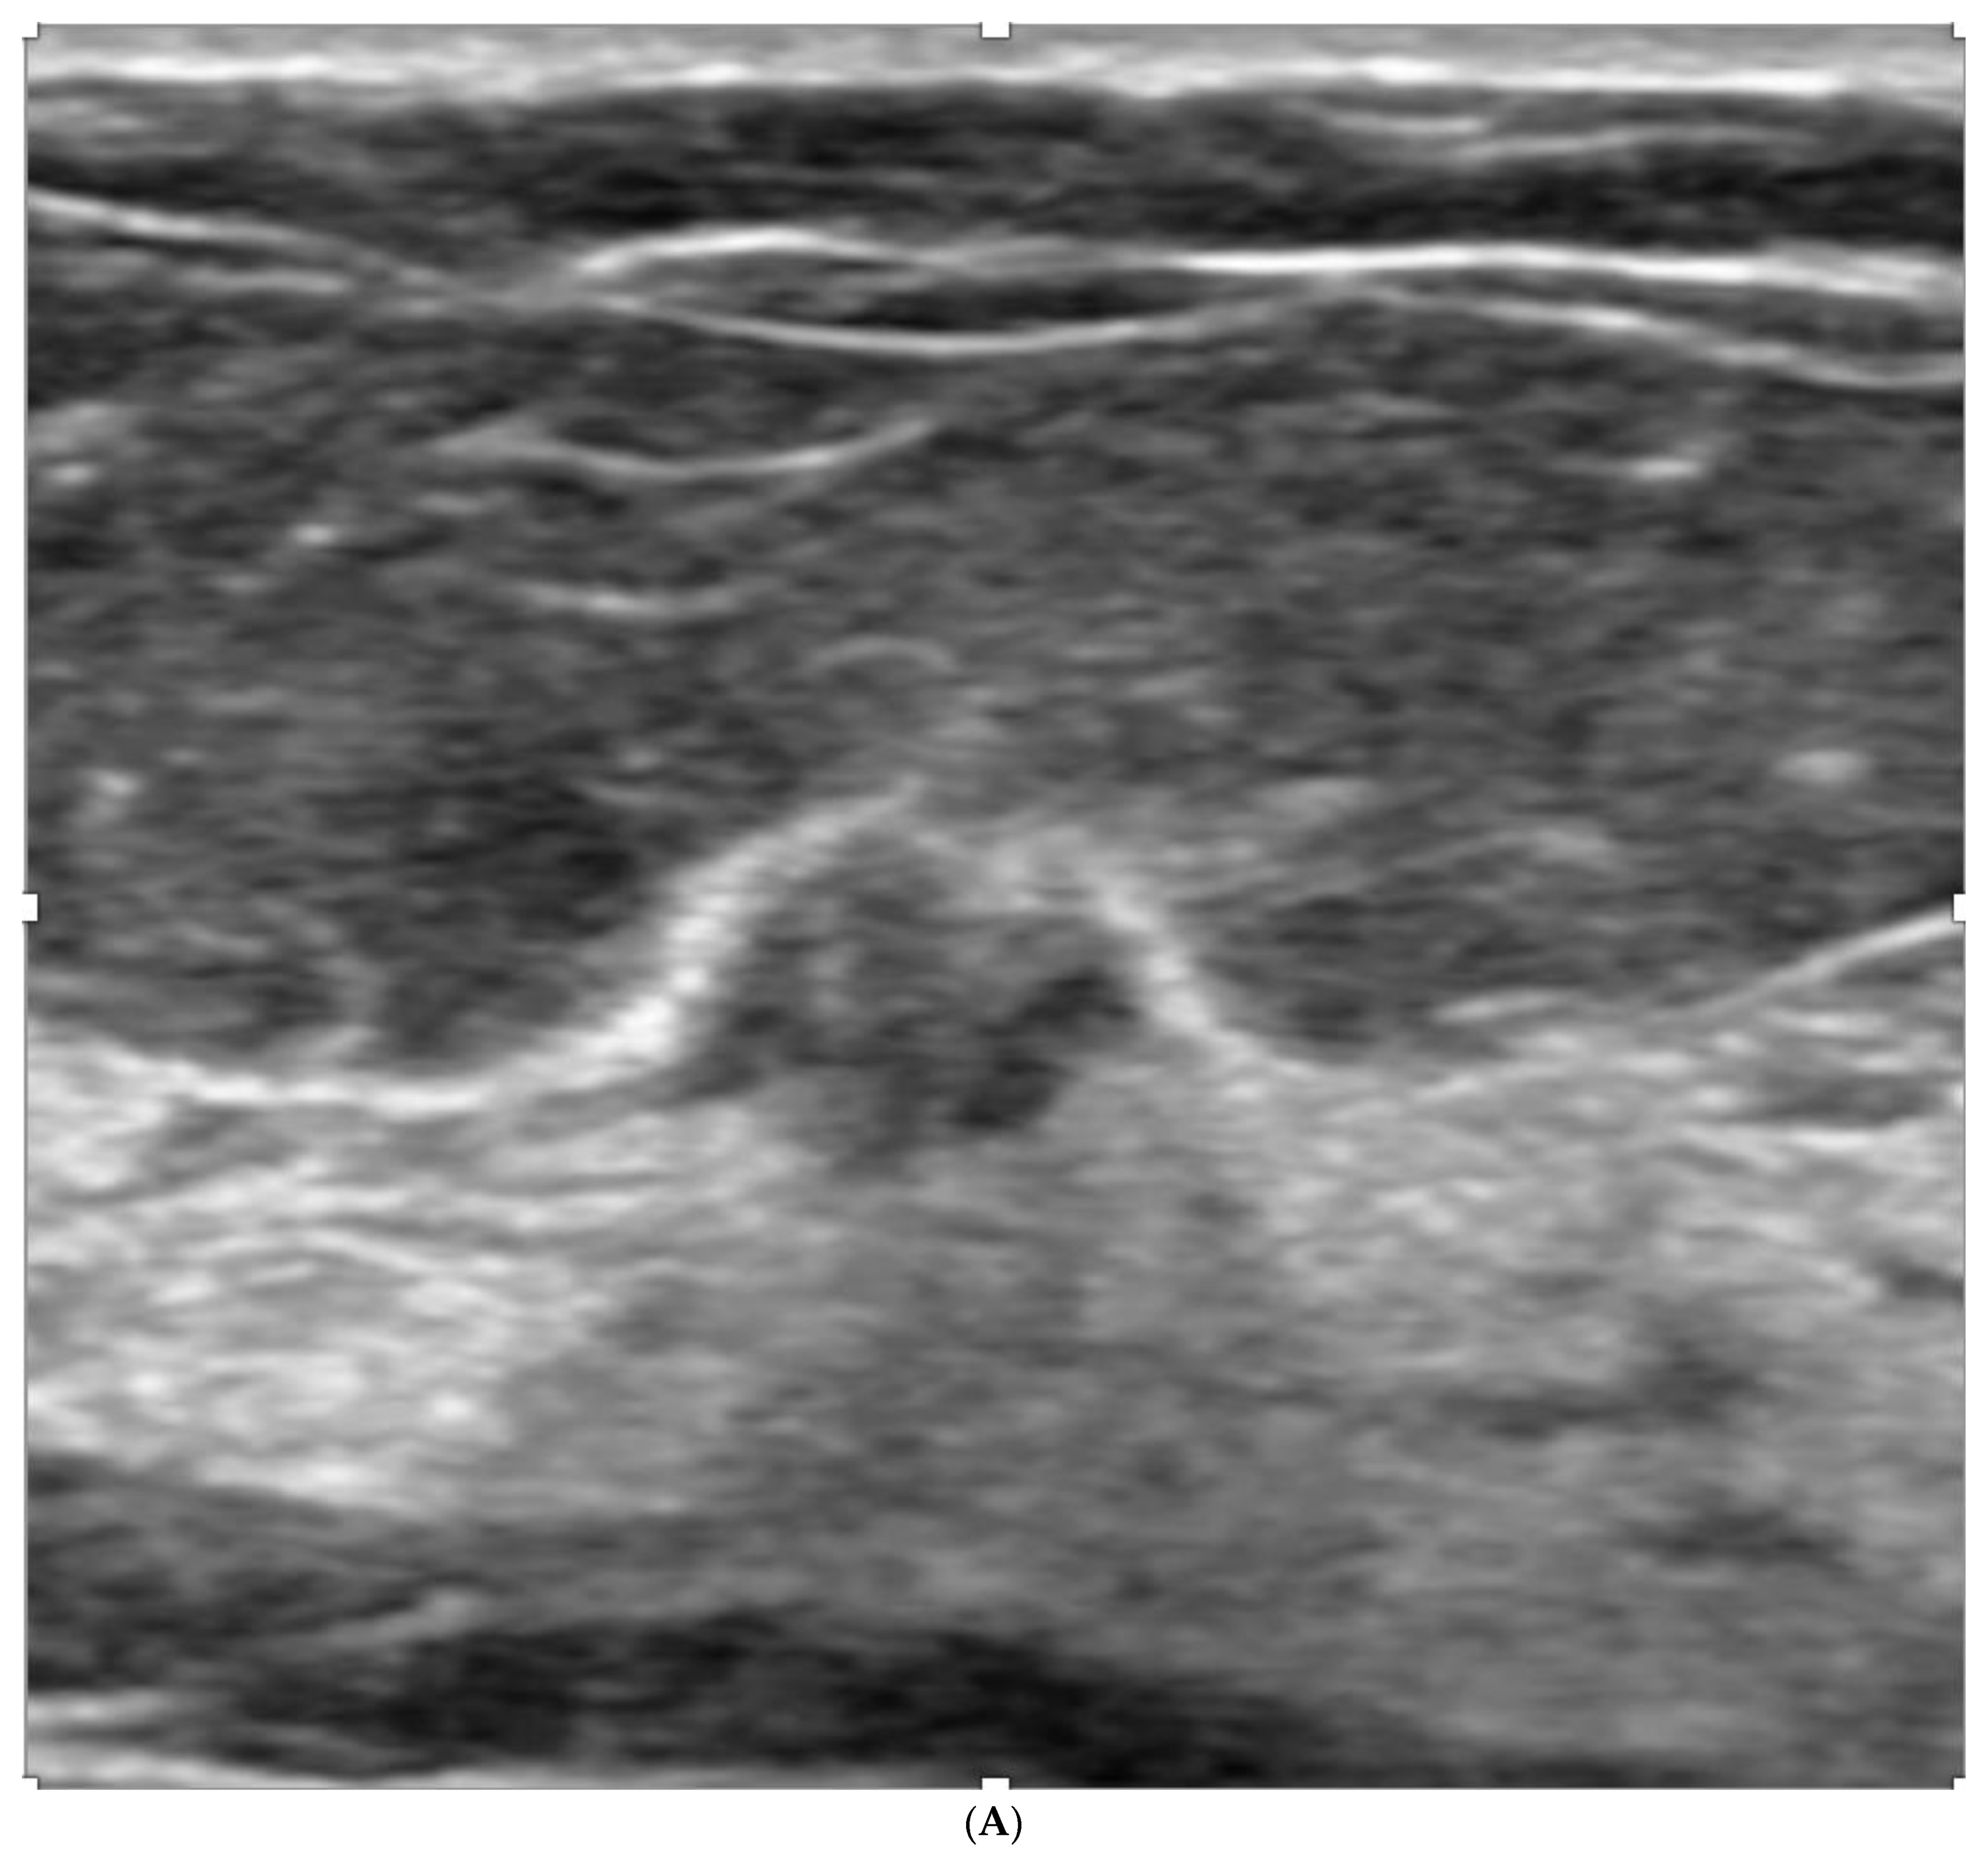

6. Digital Breast Tomosynthesis (DBT)